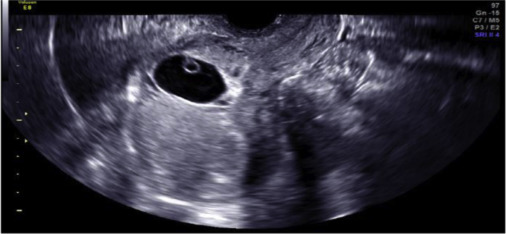

La ecografía es la modalidad de imagen primaria para el diagnóstico de embarazo por cicatriz cesárea, aunque una determinación correcta y oportuna puede ser difícil. Se han descrito terapias quirúrgicas, médicas y mínimamente invasivas para el manejo del embarazo por cicatrización por cesárea, pero no se conoce el tratamiento óptimo. Las mujeres que rechazan el tratamiento de un embarazo en cicatriz de cesárea deben recibir asesoramiento sobre el riesgo de morbilidad severa.